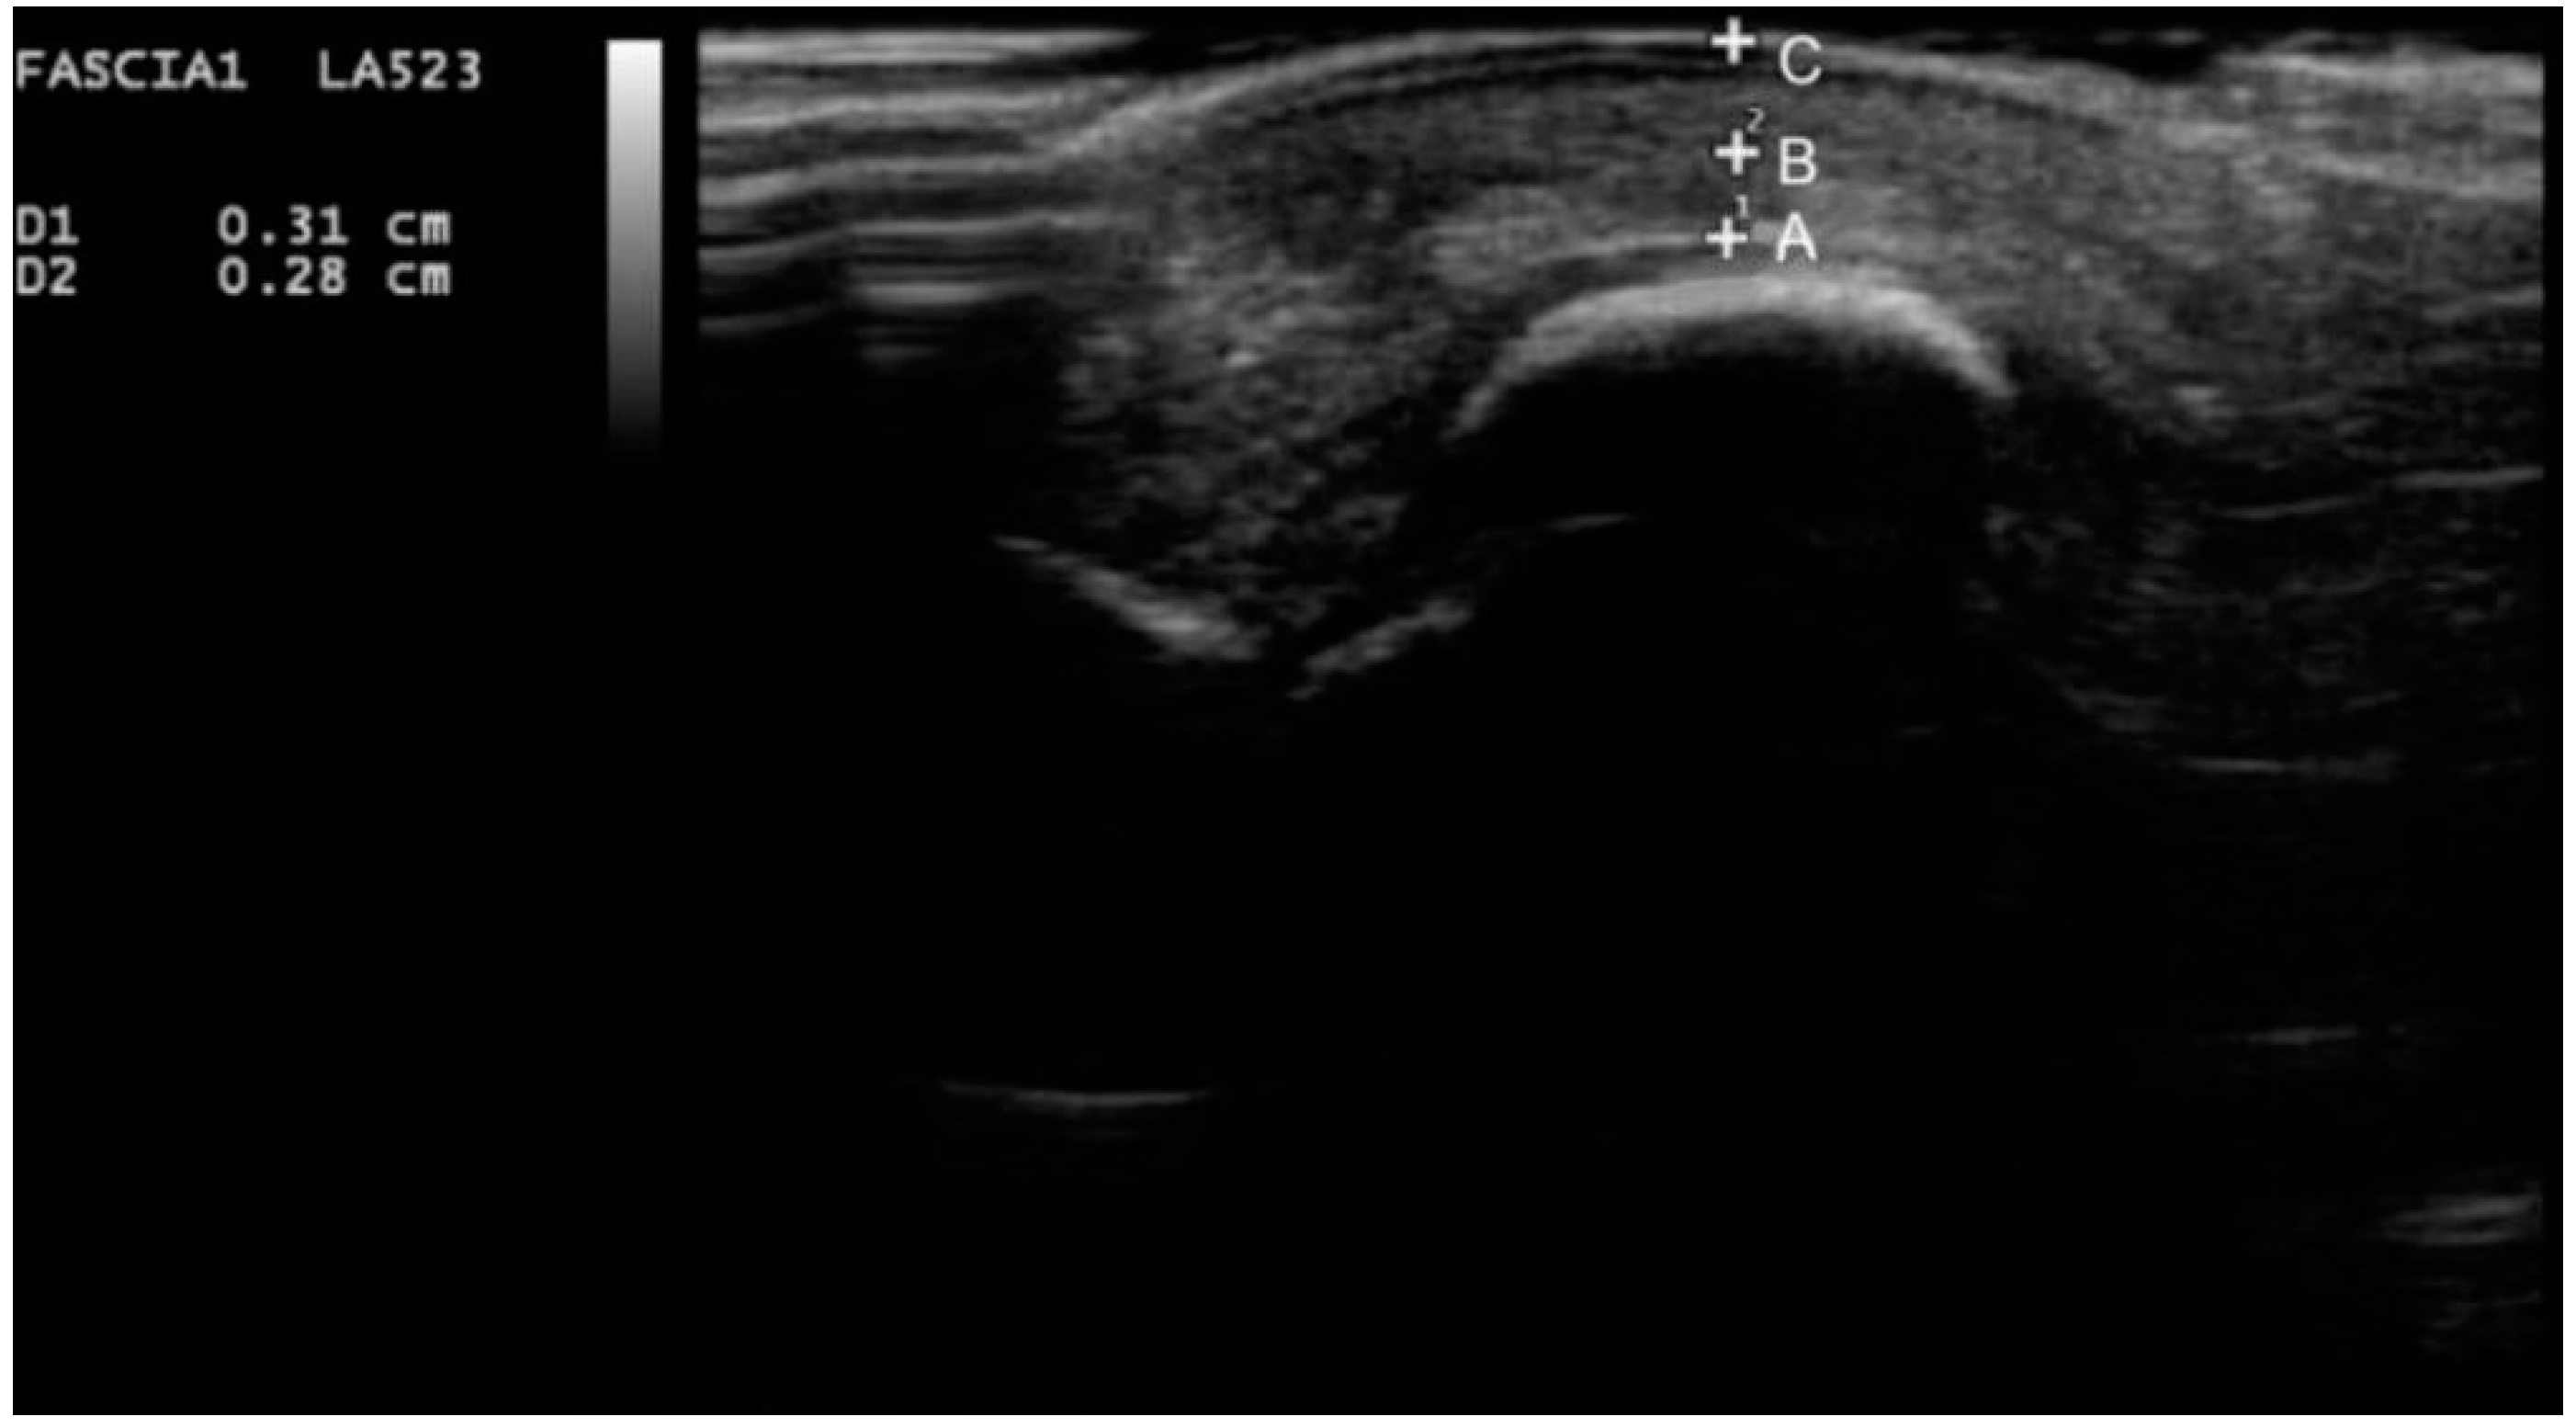

2. Experimental Section